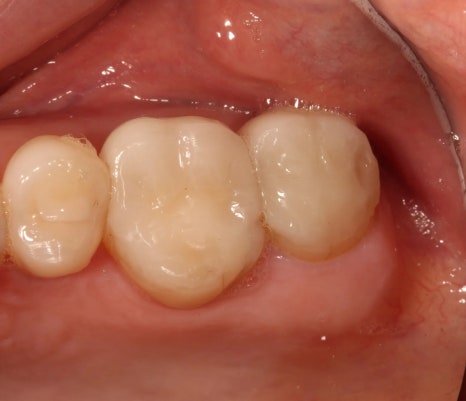

제 어금니 미니쉬 전후예요.

그래서 저는 어금니를 복구하기로 했고 총 4개의 어금니 미니쉬를 받았어요.

결과적적으로 치아의 기능은 안정되었고 심미적으로는 훨씬 자연스러워졌어요.

지금은 교합도 편안하고 자신 있게 웃고 있답니다.

왜냐하면 어금니에 미니쉬를 한 지 벌써 6년이 지났는데, 앞니보다 3배 이상 강한 힘을 받는 어금니에서도 깨짐이 전혀 없었거든요.

앞니보다 훨씬 큰 힘을 받는 어금니에 미니쉬를 한 지 벌써 6년이 지났는데 지금도 멀쩡하게 잘 쓰고 있기 때문이에요.